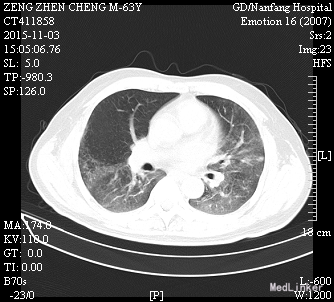

患者诉仍有咳嗽咳痰、呼吸困难、胸闷气促,咳白色粘痰,平卧及活动时加重,坐起后缓解,无发热,无咯血,精神、睡眠一般,饮食欠佳,大小便正常。高流量吸氧(7L/min)下血氧饱和度维持在93-95%,心率65-75次/分。查体:神志清楚,查体合作,胸廓未见异常;双肺呼吸音粗,双侧肺可闻及少许细湿罗音,无胸膜摩擦音;心界不大,心律齐,各瓣膜听诊区未闻及病理性杂音;腹平坦,无压痛、反跳痛,肝脏肋下未触及。辅助检查:感染三项:降钙素原(ProCT)6.00ng/ml;淀粉样蛋白A(SAA)281.8mg/L;C反应蛋白(CRP)。真菌D-葡聚糖(1_2_3βD)315pg/mL。巨细胞病毒定量(FQ_HCMV)2.85E+3copies/m。凝血功能:血浆D-二聚体测定(D-Dimer)0.85mg/L FEU;活化部分凝血活酶时间(APTT)46.8秒;血浆凝血酶原时间测定(PT)14.0秒。肾功能:尿素(BUN)19.52mmol/L;肌酐(CR)223μmol/L。肝功能:丙氨酸氨基转移酶(ALT)79U/L;天门冬氨酸氨基转移酶(AST)60U/L;总蛋白(TP)54.3g/L;白蛋白(ALB)21.8g/L150.67mg/L。前-脑利尿肽(Pro-BNP)572.1pg/mL。胸片示:1、两肺炎症,较前进展,建议治疗后复查;2、主动脉硬化;3、左肾区致密影,请结合临床其他检查;4、右第4肋骨陈旧骨折。

肾移植术后肺 部感染多发生在术后的早期,多数是在术后2~4月期间感染的。与这期间免疫抑制剂用量大,机体抵抗力低下有关。新型免疫抑制剂的临床应用,提高了肾移植的成功率,但也导致了机体免疫力降低,增加了各种感染的机会,以肺部感染最为常见,已成为肾移植患者死亡的主要原因。早期诊断和治疗对其预后尤为重要。 肾移植术后肺部感染早期的临床表现往往不典型,发热是其最常见、最主要的早期症状有发热,占 90%;许多患者入院时只有发热,开始为低热,咳嗽、咯痰、双 肺罗音均不明显,随后3-5天体温可达38.5℃以上;X线胸片已经显示肺部有点、片状阴影;病情发展迅速,咳嗽、咯痰及肺部罗音出现,患者很快会出现胸闷、呼吸困难、血氧饱和度下降,血气分析可有不同程度的低氧血症。所以肾移植术后早期出现发热,一定要摄胸片(或反复摄胸片),查白细胞计数,必要时行纤维支气管镜检查,或按肺部感染处理(排除排异反应)。 病原体的检测至关重要,需要反复、多次查血和痰的细菌、霉菌培养、痰涂片,必要时可行纤维支气管镜取分泌物查找病原菌。肾移植术后病毒感染较常见,特别是巨细胞病毒(CMV)最常见;由于CMV在正常人群中广泛存在,但多无临床症状,在免疫力低下时可使潜在的病毒复活、复制,导致肺部感染,死亡率高。激素对潜在的CMV复活影响很小,免疫抑制剂(如CSA、FK506等)可加速CMV的复制;CMV肺部感染无特异性,表现为高热、干咳、呼吸急促、白细胞减少,胸片多以片状或散在点片状影为主,也可扩散至全肺,呈间质性肺炎的表现;虽然获得CMV感染的直接证据很难,但PCR-CMV -DNA和CMV-IgM的检测可作为诊断依据。更昔洛韦对CMV感染治疗效果较好。 肾移植患者由于长期大量的用免疫抑制剂、肾上腺皮质激素,使机体抵抗力下降,加之强效广谱抗生素的应用,易造成机体菌群失调,导致二重感染,使机体正常分布的真菌大量繁殖、扩散。可适当抢先治疗,本例用卡泊芬净取得较好效果。肾移植术后肺部感染患者病情进展迅速,伴随着高热,可出现胸闷、呼吸困难、血氧饱和度下降等;治疗上除抗感染、化痰止咳外,必要 用呼吸机辅助呼吸,改善肺通气功能,提高血氧分压;可先采用无创的面罩吸氧,如氧合不满意,则改用有创的气管插管辅助通气,本例患者用无创呼吸机辅助通气取得较好效果。